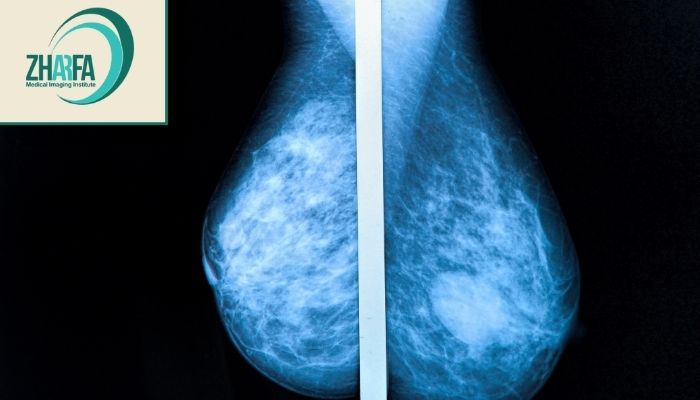

ماموگرافی یکی از روش‌های تصویربرداری پزشکی است که با استفاده از اشعه ایکس به تشخیص زودهنگام سرطان سینه کمک می‌کند. با این حال بسیاری از زنان نگران درد یا ناراحتی احتمالی در طول این آزمایش هستند. تجربه درد در تصویربرداری پستان برای هر فرد متفاوت است. برخی زنان ممکن است در طول این فرآیند احساس درد کنند و برخی دیگر اصلاً چیزی احساس نکنند. اکثر خانم‌ها در طی فرآیند تابش اشعه ایکس احساس ناراحتی می‌کنند. فشار وارد شده بر سینه شما از طرف تجهیزات آزمایشگاهی می‌تواند باعث درد یا ناراحتی شود و این طبیعی است. این قسمت از فرآیند باید فقط چند دقیقه طول بکشد. هنوز هم بقیه خانم‌ها در طول این آزمایش درد شدیدی احساس می‌کنند. میزان درد شما ممکن است بسته به موارد زیر در هر تصویربرداری پستان متفاوت باشد:

ماموگرافی شاید برای بعضی خانم‌ها با کمی فشار یا ناراحتی همراه باشد اما این احساس معمولاً کوتاه‌مدت، قابل تحمل و با چند اقدام ساده قابل کنترل است. شدت درد در افراد مختلف متفاوت است و به عواملی مثل زمان چرخه قاعدگی، سایز و تراکم پستان، میزان استرس و تجربه تیم تصویربرداری بستگی دارد. با این حال اهمیت تشخیص زودهنگام سرطان پستان بسیار بیشتر از این ناراحتی گذراست. انتخاب زمان مناسب، آرامش ذهنی، اطلاع‌رسانی به تکنسین و در صورت نیاز مصرف مسکن ساده می‌تواند تجربه‌ای راحت‌تر ایجاد کند. از سوی دیگر فشرده‌سازی پستان در تصویربرداری پستان برای گرفتن تصاویر دقیق، کاهش میزان اشعه و جلوگیری از تکرار عکس‌برداری ضروری است. در نهایت غربالگری پستان یک روش ایمن، استاندارد و حیاتی برای حفظ سلامت زنان است. هرگونه ناراحتی موقت در برابر مزایای بزرگ آن یعنی کشف زودهنگام سرطان و افزایش شانس درمان موفق، ارزشمند و قابل چشم‌پوشی است.